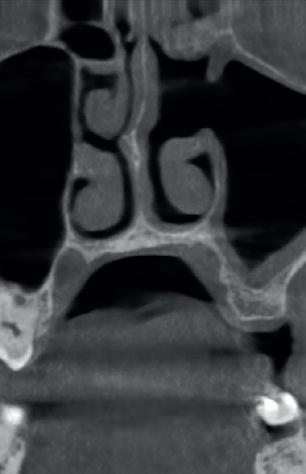

Lâexamen exobuccal Ă©tait sans particularitĂ©s. Lâexamen endobuccal a objectivĂ© une inflammation marginale modĂ©rĂ©e Ă sĂ©vĂšre gĂ©nĂ©ralisĂ©e avec un indice dâOleary Ă 68%, un indice gingival (BoP = Bleeding on Probing) Ă 76%, et un trama occlusal sur 42 (Figure 1). Le bilan parodontal montre des sites avec une profondeur de sondage (PS) de 12mm, et plus de 50% des dents prĂ©sentant une perte dâattache â„ 5mm. Le bilan radiographique a montrĂ© des pertes osseuses terminales, avec un rapport perte osseuse/Ăąge Ă 4,5 (Figure 1)

Le diagnostic de parodontite stade IV grade C généralisé a été proposé (1), avec un pronostic irrationnel au traitement pour les dents 25, 36, 42 et défavorable pour 11, 21, 35, 46 (2).

La thĂ©rapeutique Ă©tiologique a consistĂ© en une Ă©ducation Ă lâhygiĂšne bucco-dentaire, une Ă©limination des facteurs de rĂ©tention de plaque, lâextraction 42+rĂ©section radiculaire et rĂ©alisation dâune contention en fibre de verre avec la couronne ; dâune instrumentation non chirurgicale supra et sous gingivale

par quadrant (3) combinĂ©e Ă une antibiothĂ©rapie (3,4). Une chirurgie avec lambeau dâaccĂšs selon la technique du lambeau avec incision intrasulculaire (open flap) a Ă©tĂ© rĂ©alisĂ©e sur la 46. Une thĂ©rapie parodontale de soutien associĂ©e Ă une phase correctrice a Ă©tĂ© mise en place aprĂšs la thĂ©rapie parodontale active (5). La rĂ©habilitation orale a consistĂ© dans un premier temps Ă rĂ©aliser une correction orthodontique (Figure 2) ; et dans un second temps la conception dâune Ă©pithĂšse gingivale (Figure 3)

AprĂšs 6 mois, pas de profondeurs de poches â„ 6mm, avec un indice de plaque Ă 9% et un indice gingival < 10%. La thĂ©rapeutique non chirurgicale a permis un gain dâattache

stable qui sâest traduit par une diminution des profondeurs de sondage en regard de la 11, 21, et 36 dont le pronostic Ă©tait dĂ©favorable, mais aussi lâapparition dâimportantes rĂ©cessions postthĂ©rapeutique (Figure 4). La chirurgie avec lambeau dâaccĂšs a permis Ă©galement dâamĂ©liorer le niveau osseux de la 46. Le pronostic gĂ©nĂ©ral Ă long terme de la patiente a Ă©tĂ© amĂ©liorĂ©.